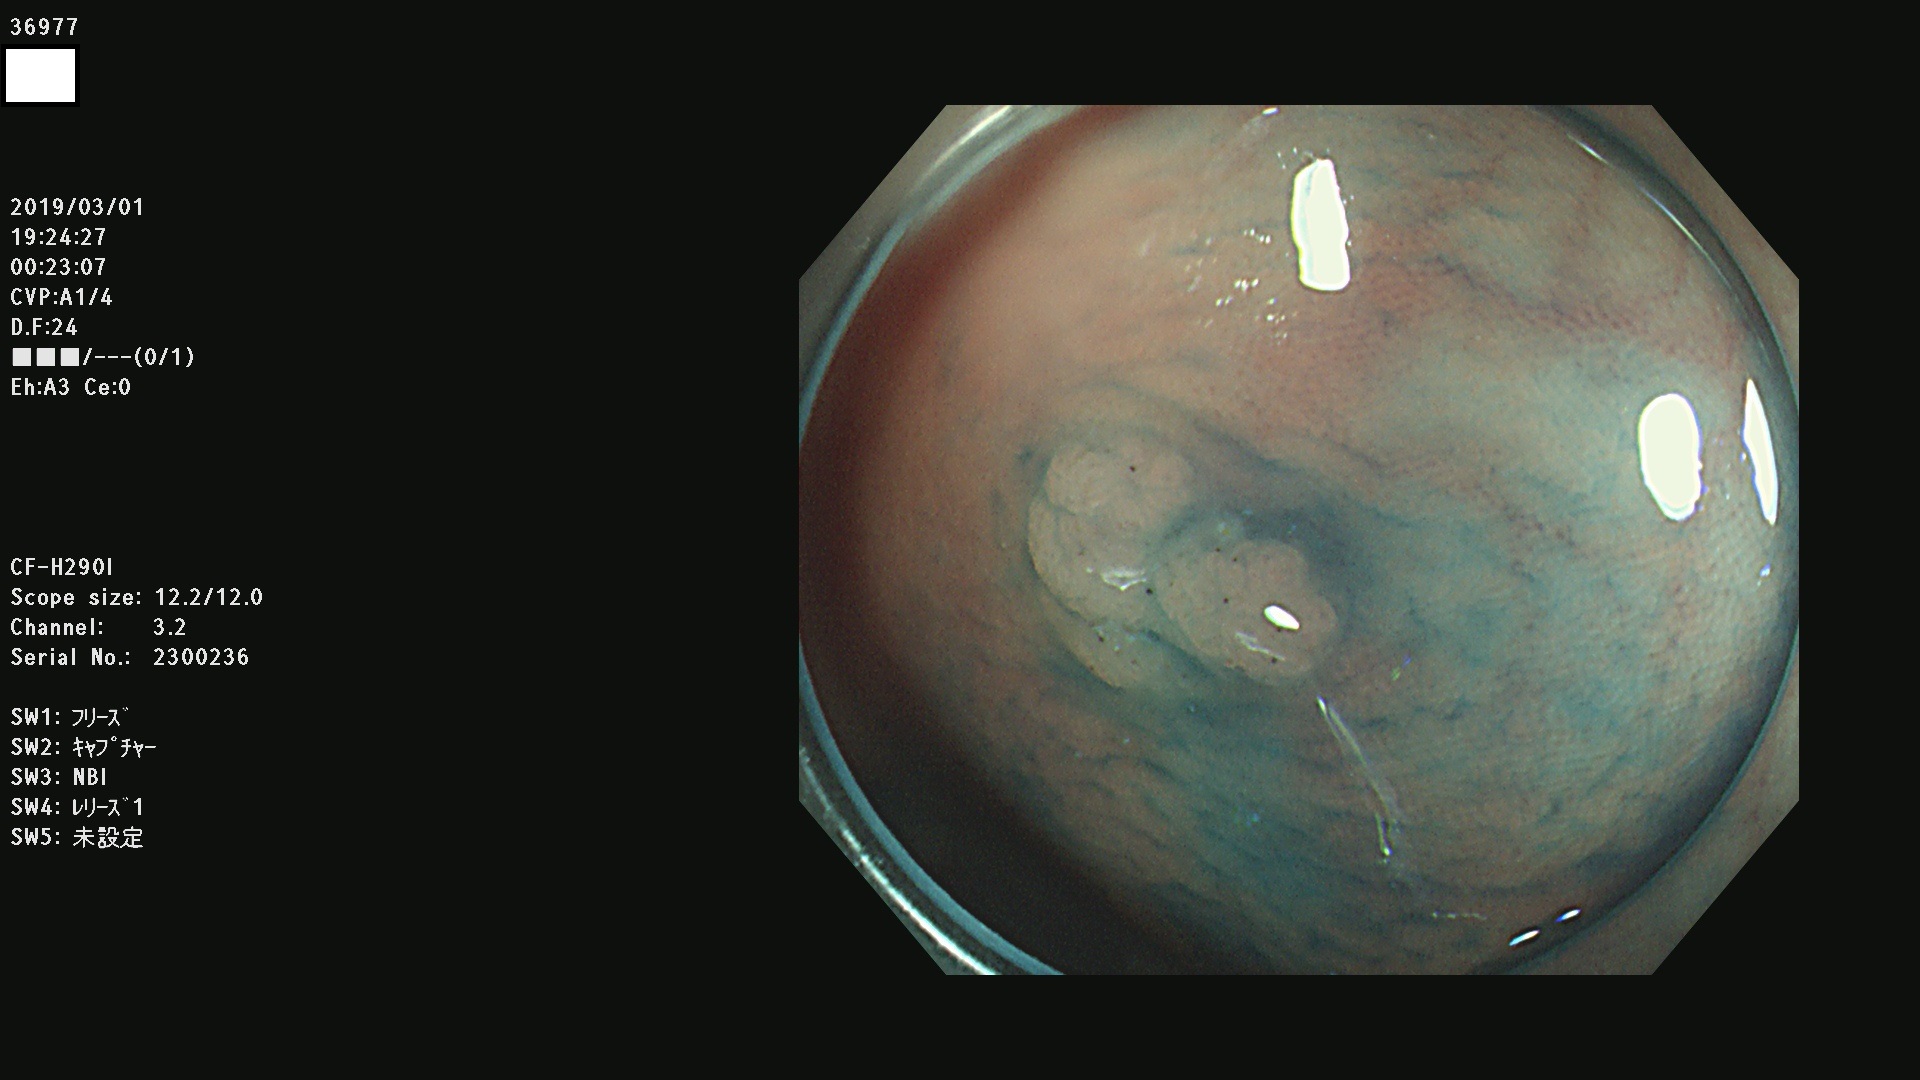

発見困難で危険性の高い平坦型病変(上記100名より抽出) ![]()